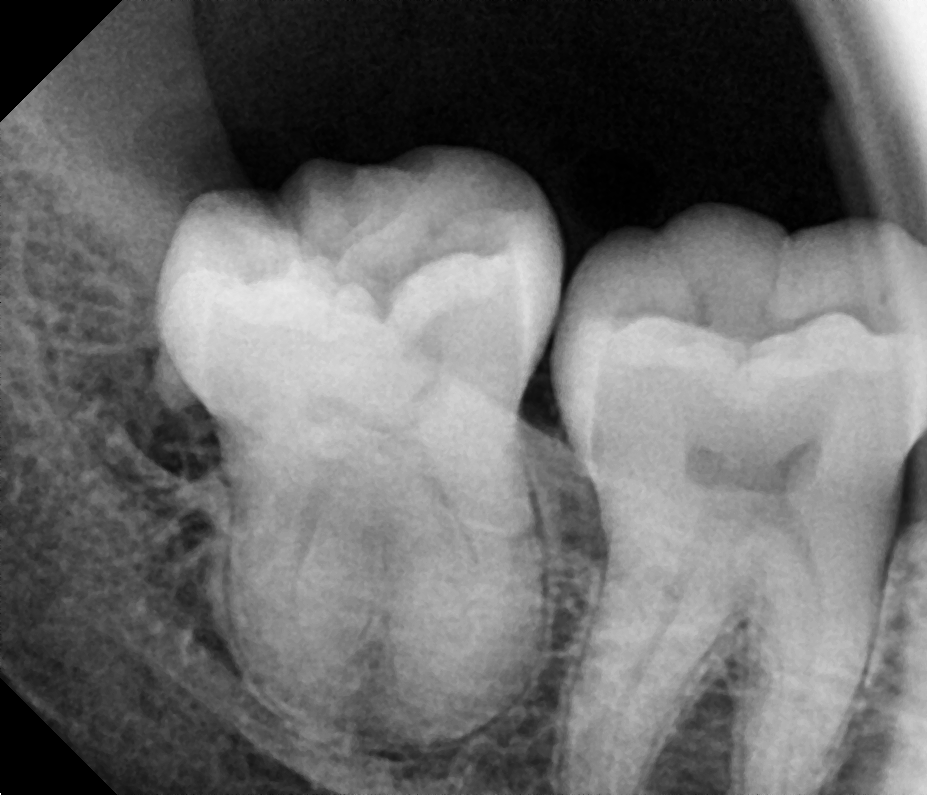

Mesioangular

After After

Before Before